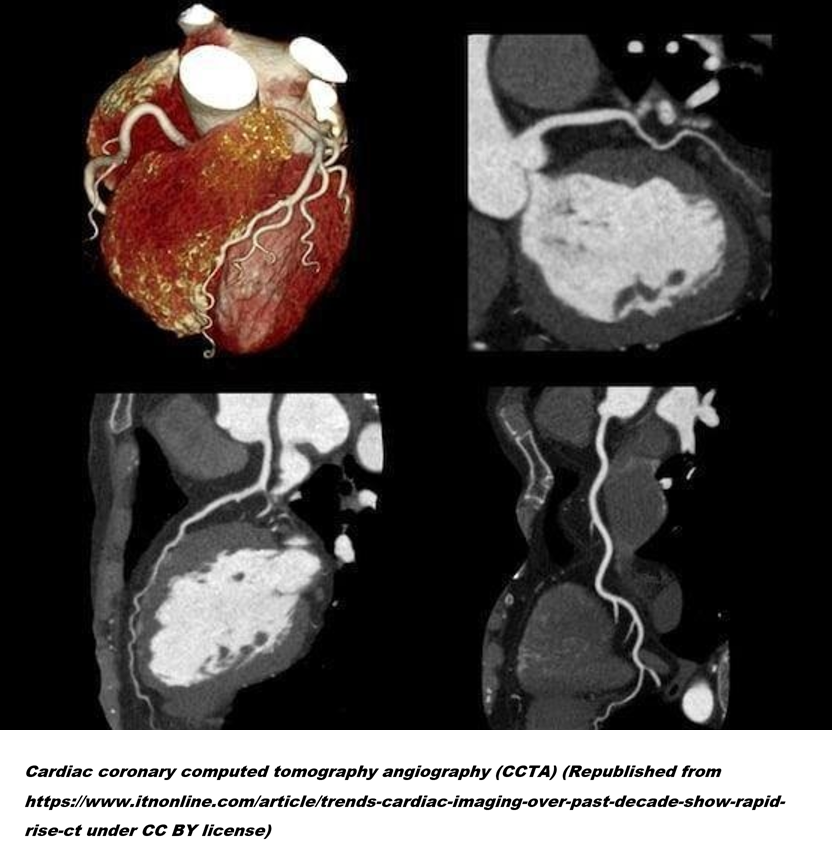

3. 협심증 환자의 표준 진단법으로 자리 잡고 있는 관상동맥 CT조영술(CCTA)에 대해 먼저 다루긴 했지만, 실제 건강검진에서 주로 시행되는 검사는 조영제를 사용하지 않는 일반 관상동맥 CT인 경우가 많습니다. 두 검사의 차이는 조영제를 쓰느냐 마느냐인데, CCTA와 비교해 일반 CT는 방사선 조사량이 적고, 조영제 부작용도 걱정하지 않아도 될뿐더러, 검사를 받는 것도 훨씬 편하다는 장점이 있습니다. 그 대신 조영제를 쓰지 않으니 혈관자체를 들여다볼 수는 없습니다.

4. 반대로 혈관 상태를 직접 들여다볼 수 있는 CCTA 검사는 맥박수를 낮춰야 해서 베타 차단제를 먹어야 하며 검사 중에 숨도 오래 참을 수 있어야 합니다. 아무래도 심장은 쉬지 않고 움직이는 장기다 보니 멈춘 장면을 잘 찍어내려면 셔터 속도를 빠르게 하는 것도 중요하지만, 좀 천천히 움직이게 하는 것도 중요하기 때문입니다. 이런저런 이유로 증상이 없는 일반인의 심혈관 위험도를 예측(Risk Stratification)하는 목적으로 가이드라인에서도 CCTA가 아닌 일반 CT를 권고하고 있습니다.

CCTA.png